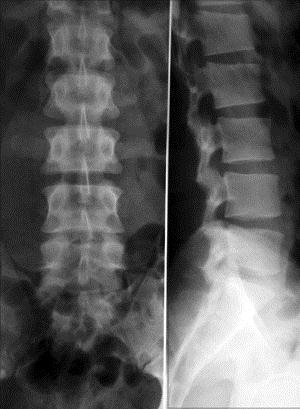

问题 病历摘要: 患者男性,45岁,因反复腰痛、右腿麻痛2个月入院。查体:腰椎向左侧弯,L/L棘突间隙有压痛和叩击痛,右小腿外侧皮肤感觉减退,右下肢直腿抬高试验(+)。 该患者的诊断是: 提示:腰椎 X线片、CT片如图:

选项 A、L/L水平椎管肿瘤 B、腰椎椎管狭窄症 C、腰椎结核 D、L/L椎间盘突出症